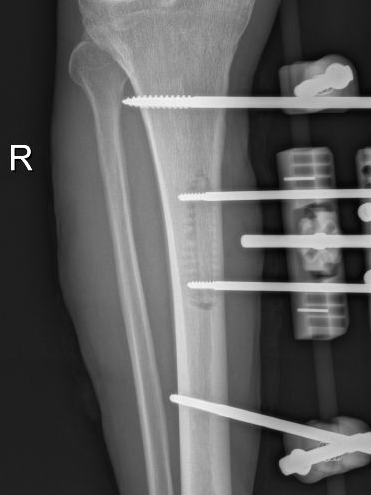

4月23日,贵州航天医院第58次晨读会由我院骨科副主任医师张艳金作学术交流,他以“加速康复指导下的快速手术”为题,详细讲解了老年股骨粗隆间骨折与儿童四肢骨折的临床诊疗难点,结合加速康复外科(ERAS)核心理念,重点阐述了ERAS理念在两大人群中的创新实践,实现患者入院后6至24小时内即可接受手术治疗。针对老年髋部骨折患者,提出通过多学科协作(MDT)与微创手术优化围术期管理,在确保安全前提下缩短术前等待时间,实施精准化麻醉及术后康复方案,可有效降低并发症发生率、改善患者生活质量和预后效果。在儿童骨折领域,强调微创术式与心理干预并行的双轨策略,既减少手术创伤对骨骼发育的影响,同时关注患儿心理疏导,实现生理功能与心理健康同步康复。并通过典型案例的影像学资料与随访数据,直观展示了ERAS理念指导下骨科治疗模式的创新成果。 贵州航天医院骨科 专家简介 赵学平 中共党员,骨科党支部书记、主任,主任医师 临床擅长:从事骨科临床工作30余年,对骨科常见疾病的诊治具有丰富的临床经验。 世界中医药联合会脊柱康复专业委员会常务理事,中华中医药学会整脊分会常务委员,中国中西医结合学会骨伤科分会肢体矫形功能重建与康复专家委员会常务委员,中国研究性医院学会骨科创新与转换专业委员会关节外科学组保髋工作委员会常委,中国康复技术转化及发展促进会骨外科与康复技术转化专业委员会常务委员,泛珠三角区域运动医学联盟(PPRD-SMA)理事会常务理事,中国研究型医院学会运动医学专业委员会委员,贵州省中医药学会整脊分会副主任委员,贵州省中西医结合学会银质针专业委员会副主任委员,贵州省康复医学会骨与关节专业委员会常务委员,贵州省人民医院骨科专科联盟常务理事,贵州省康复医学会骨内科专业委员会常务委员,中华医学会贵州省骨科学会委员,贵州省康复医学会脊柱脊髓专业委员会常务委员,贵州省运动医学分会委员,贵州省康复医学会骨与软组织肿瘤专业委员会委员,遵义市医学会创伤分会副主任委员,贵州省康复医学会骨内科专业委员会遵义地区分会常务委员,遵义市医疗事故鉴定、伤残鉴定、工伤鉴定、司法鉴定专家。 长期从事骨科临床研究及教学工作,在国家级、省部级杂志发表论文20余篇,SCI论文2篇,参与主编骨科专著2部,主持省部级科研项目2项,参与指导省部级、市级科研项目6项。 陈明勇 骨科副主任,副主任医师 临床擅长:从事创伤骨科工作约20年,对骨缺损、骨不连、骨肿瘤、肢体畸形等的肢体矫形重建及功能重建,慢性化脓性骨髓炎的根治治疗、糖尿病足的保肢治疗、快速康复理念(ERAS)下的老年骨折的诊治,四肢复杂骨折的诊治,四肢骨折等微创手术治疗具有丰富的临床经验。 2004年毕业于遵义医学院临床专业,曾在中国人民解放军总医院、广西医科大学第一附属医院、上海第六人民医院骨科进修。中国中西医结合学会骨伤科专业委员会横向骨搬移治疗糖尿病足及微血管网再生学组首届委员,遵义市医学会创伤分会常务委员。 瞿 辉 中共党员,骨科副主任医师 临床擅长:对骨科的常见病、关节外科、脊柱外科及运动医学疾病的诊治具有丰富的临床经验,熟练掌握骨科手术操作技术。 毕业于遵义医学院临床医学系,2005年前往广州中山大学第一附院骨显微医学部进修学习,2011年前往成都华西医院进修学习,并多次在省内外学习骨科相关知识,是中华医学会骨科分会会员。 赵兴东 骨科主任医师 临床擅长:擅长骨科的常见病及各种创伤、四肢骨折创伤修复、骨感染、手足疾病的诊治和手足体表畸形的矫形整复,熟练掌握骨科四肢骨病及创伤的手术操作技术,尤其在四肢关节复杂性损伤、手足外伤、组织缺损创面、难治创面的皮瓣修复方面及平足、高弓足矫形方面及四肢慢性疼痛诊治、康复方面具有丰富的临床经验。 硕士研究生,毕业于遵义医学院临床外科系,2015年前往山东省立医院手足外科进修学习;遵义市医学分会创伤分会第一、二届委员,遵义市手外科医学会第二委届员会常务委员;在省级及省级以上期刊发表文章9篇,参编著作2部,参与主持并完成市级课题1项,参与市级课题2项、省级课题1项。 张艳金 中共党员,骨科副主任医师 临床擅长:从事骨外科工作16年,对复合伤、多发伤的救治、四肢骨干骨折、关节周围骨折、骨肿瘤、骨髓炎等诊治具有丰富的临床经验。 中共党员,硕士研究生,2006年本科毕业于山西医科大学第二临床医学院,2011年研究生毕业于北京军区总医院;在“老年COPD患者合并髋部骨折的诊治”国际合作课题组研究两年,在老年髋部骨折的诊治方面具有丰富的经验,并发表论文6篇;主持遵义市级课题1项,承担遵义医科大学的临床教学工作,获得遵义医科大学优秀带教老师荣誉。编撰有《骨科疾病诊疗精粹》一书,开展2项新技术,编撰地方规范《务川自治县创伤骨科常见疾病诊疗规范》一书。 张俊凯 骨科副主任医师 临床擅长:从事骨科临床工作28年,对创伤骨折、骨感染、骨缺损、骨不连等外科诊治,四肢骨折的微创手术治疗,四肢复杂骨折(如关节内粉碎性骨折、多发骨折等)的损伤控制及手术治疗等具有丰富的临床经验。 1995年毕业于遵义医学院临床专业,2009年前往复旦大学附属医院骨科进修1年。 卢懿明 中共党员,骨科副主任医师 临床擅长:从事骨科工作18年,对创伤骨折、四肢骨折的微创手术治疗、四肢复杂骨折(如关节内粉碎性骨折、多发骨折等)的损伤控制及手术治疗,尤其是髋部骨折的PFNA等微创技术,踝关节骨折、膝关节周围骨折的Mipo微创技术等具有丰富的临床经验,开展了4项新技术,发明6项新型专利技术。 2005年毕业于遵义医学院临床专业,2017年,前往南方医科大学第三附属医院骨科进修半年,回院后运用Mipo技术对骨干骨折及干骺端骨折的治疗技术,同时积极开展骨盆骨折、髋臼骨折腹直肌外侧切口的应用;发表了多篇专业论文,经常参与省内外学术交流会授课,获得医院荣誉称号多个。 邬夏荣 骨科副主任医师 临床擅长:从事骨科工作16年,对四肢复杂骨折、骨肿瘤的诊治,尤其是足踝创伤、慢性踝关节损伤、平足症等诊疗具有丰富的临床经验。 2006年毕业于遵义医科大学临床医学专业,曾在陆军军医大学西南医院进修学习,发表多篇骨科学术论文。 余德怀 中共党员,骨科副主任医师 临床擅长:从事骨科工作10余年,对运动医学、骨关节、脊柱外科常见病、多发病的诊治具有丰富的临床经验。 硕士研究生,2011年毕业于遵义医学院临床医学专业,曾前往遵义医科大学附属医院运动医学专业进修学习;是贵州省医学会运动医学分会青年委员,西部关节镜联盟委员;发表多篇骨科学术论文。 冯 乾 骨科副主任医师 临床擅长:从事骨科工作近20年,熟练掌握骨科多发病及常见病的诊治,尤其对脊柱退变性疾病的诊断及治疗具有丰富的临床经验,主要研究脊柱微创相关治疗方式,能熟练开展椎间孔镜及UBE。 曾前往北京大学第三医院进修学习疼痛及椎间孔镜、首都医科大学友谊医院专业进修脊柱内镜;是贵州省康复医学会第三届脊柱脊髓专业委员会委员;发明专利3项、发表脊柱外科专业论文多篇。 赵小锋 中共党员,骨科副主任医师 临床擅长:从事骨科临床工作11年,对骨科常见病、多发病诊疗有较为丰富的临床经验,擅长脊柱相关疾病诊断及治疗,尤其是颈、腰、腿疼痛疾病诊断及治疗,擅长胸腰椎骨折微创经皮穿刺内固定术、经皮穿刺椎体成形术、经皮穿刺脊柱内镜下腰椎间盘摘除术、单纯开创腰椎间盘摘除术、腰椎滑脱复位椎间植骨椎融合内固定术、腰椎管狭窄减压融合内固定术及人工髋、膝关节置换术等。 2012年毕业于遵义医学院外科学专业硕士研究生,2019年参加“遵义市115医学人才精英计划”于上海交通大学第一附属医院培训学习,2023年于北京大学第三人民医院脊柱外科进修学习,曾获得遵义市优秀医师荣誉称号。 遵义市手外科第一届委员,遵义市医学会创伤分会第一届委员,遵义市医学会创伤分会第二届委员,贵州省康复医学会第三届脊柱脊髓专业会委员,遵义市医学会烧伤与整形外科学分会委员,发表论文5篇,其中国家级核心期刊1篇,SCI论文1篇,主持市级课题1项并结题,参与市级课题2项。 贵州航天医院骨科 简介 基本情况 贵州航天医院骨科组建于20世纪60年代,前身是以创伤和断肢(断指)再植闻名于世的上海市第六人民医院骨科,中国断肢(断指)再植的奠基者、中科院院士陈仲伟等著名专家、学者多次莅临科室指导医疗、教学,是贵州省最早拥有专业骨科技术科室之一,在70年代开展了贵州省首例断肢(断指)再植手术。组建50余年来,诊治患者已逾百万,挽救了无数的伤病员,成为了保障遵义地区人民群众健康的重要支撑。 经过几代人的不懈努力,今天的骨科,已由创伤骨科发展至骨病、骨肿瘤、骨结核等领域,现有脊柱外科、关节外科、四肢创伤、手足外科四个亚专科,成为了集医疗、教学、科研于一体的综合学科,是贵州省临床重点专科、遵义市临床重点专科、遵义市骨科临床医学中心、遵义市基层骨科专科联盟理事长单位。 科室目前开放床位110张,共有医护人员50余人,副高级以上专家18人,硕士研究生15人。拥有一流骨科医疗设备多台,每年不定期选派优秀技术骨干到全国各大知名医学院校进修、学习、参观、交流,并邀请国内、国外知名专家教授来院进行交流、指导,通过不断引进国内外先进的诊疗技术,科室医疗技术水平稳步提升,为广大人民群众提供了优质的医疗服务。 专科特色 骨一科 (一)骨缺损、骨不连的肢体与功能重建 胫骨横向骨搬移技术治疗糖尿病足: (二)慢性骨髓炎的根治治疗 (三)肢体缺血性疾病如糖尿病足、脉管炎的保肢治疗 (四)皮瓣修复 (五)复杂创伤的治疗 (六)老年髋部骨折及小儿骨折快速手术 老年髋部骨折: 骨二科 (一)胸腰椎骨折微创经皮椎弓根螺钉固定术 (二)老年性骨质疏松性患者腰椎滑脱脊柱内固定术(骨水泥螺钉) (三)V形双通道脊柱内镜技术(VBE)腰椎融合术治疗腰椎退行性疾病 (四)老年性骨质疏松性骨折(PVP/PKP)术 (五)人工髋关节置换术 (六)双侧股骨头坏死人工全髋关节置换 (七)右侧全髋置换术后假体周围骨折翻修 (八)人工膝关节置换术 (九)人工膝关节假体松动翻修 (十)关节镜技术 传统手术切口 关节镜技术切口 诊疗范围 骨一科 1.四肢创伤、矫形。 2.手、足踝外科。 骨二科 end